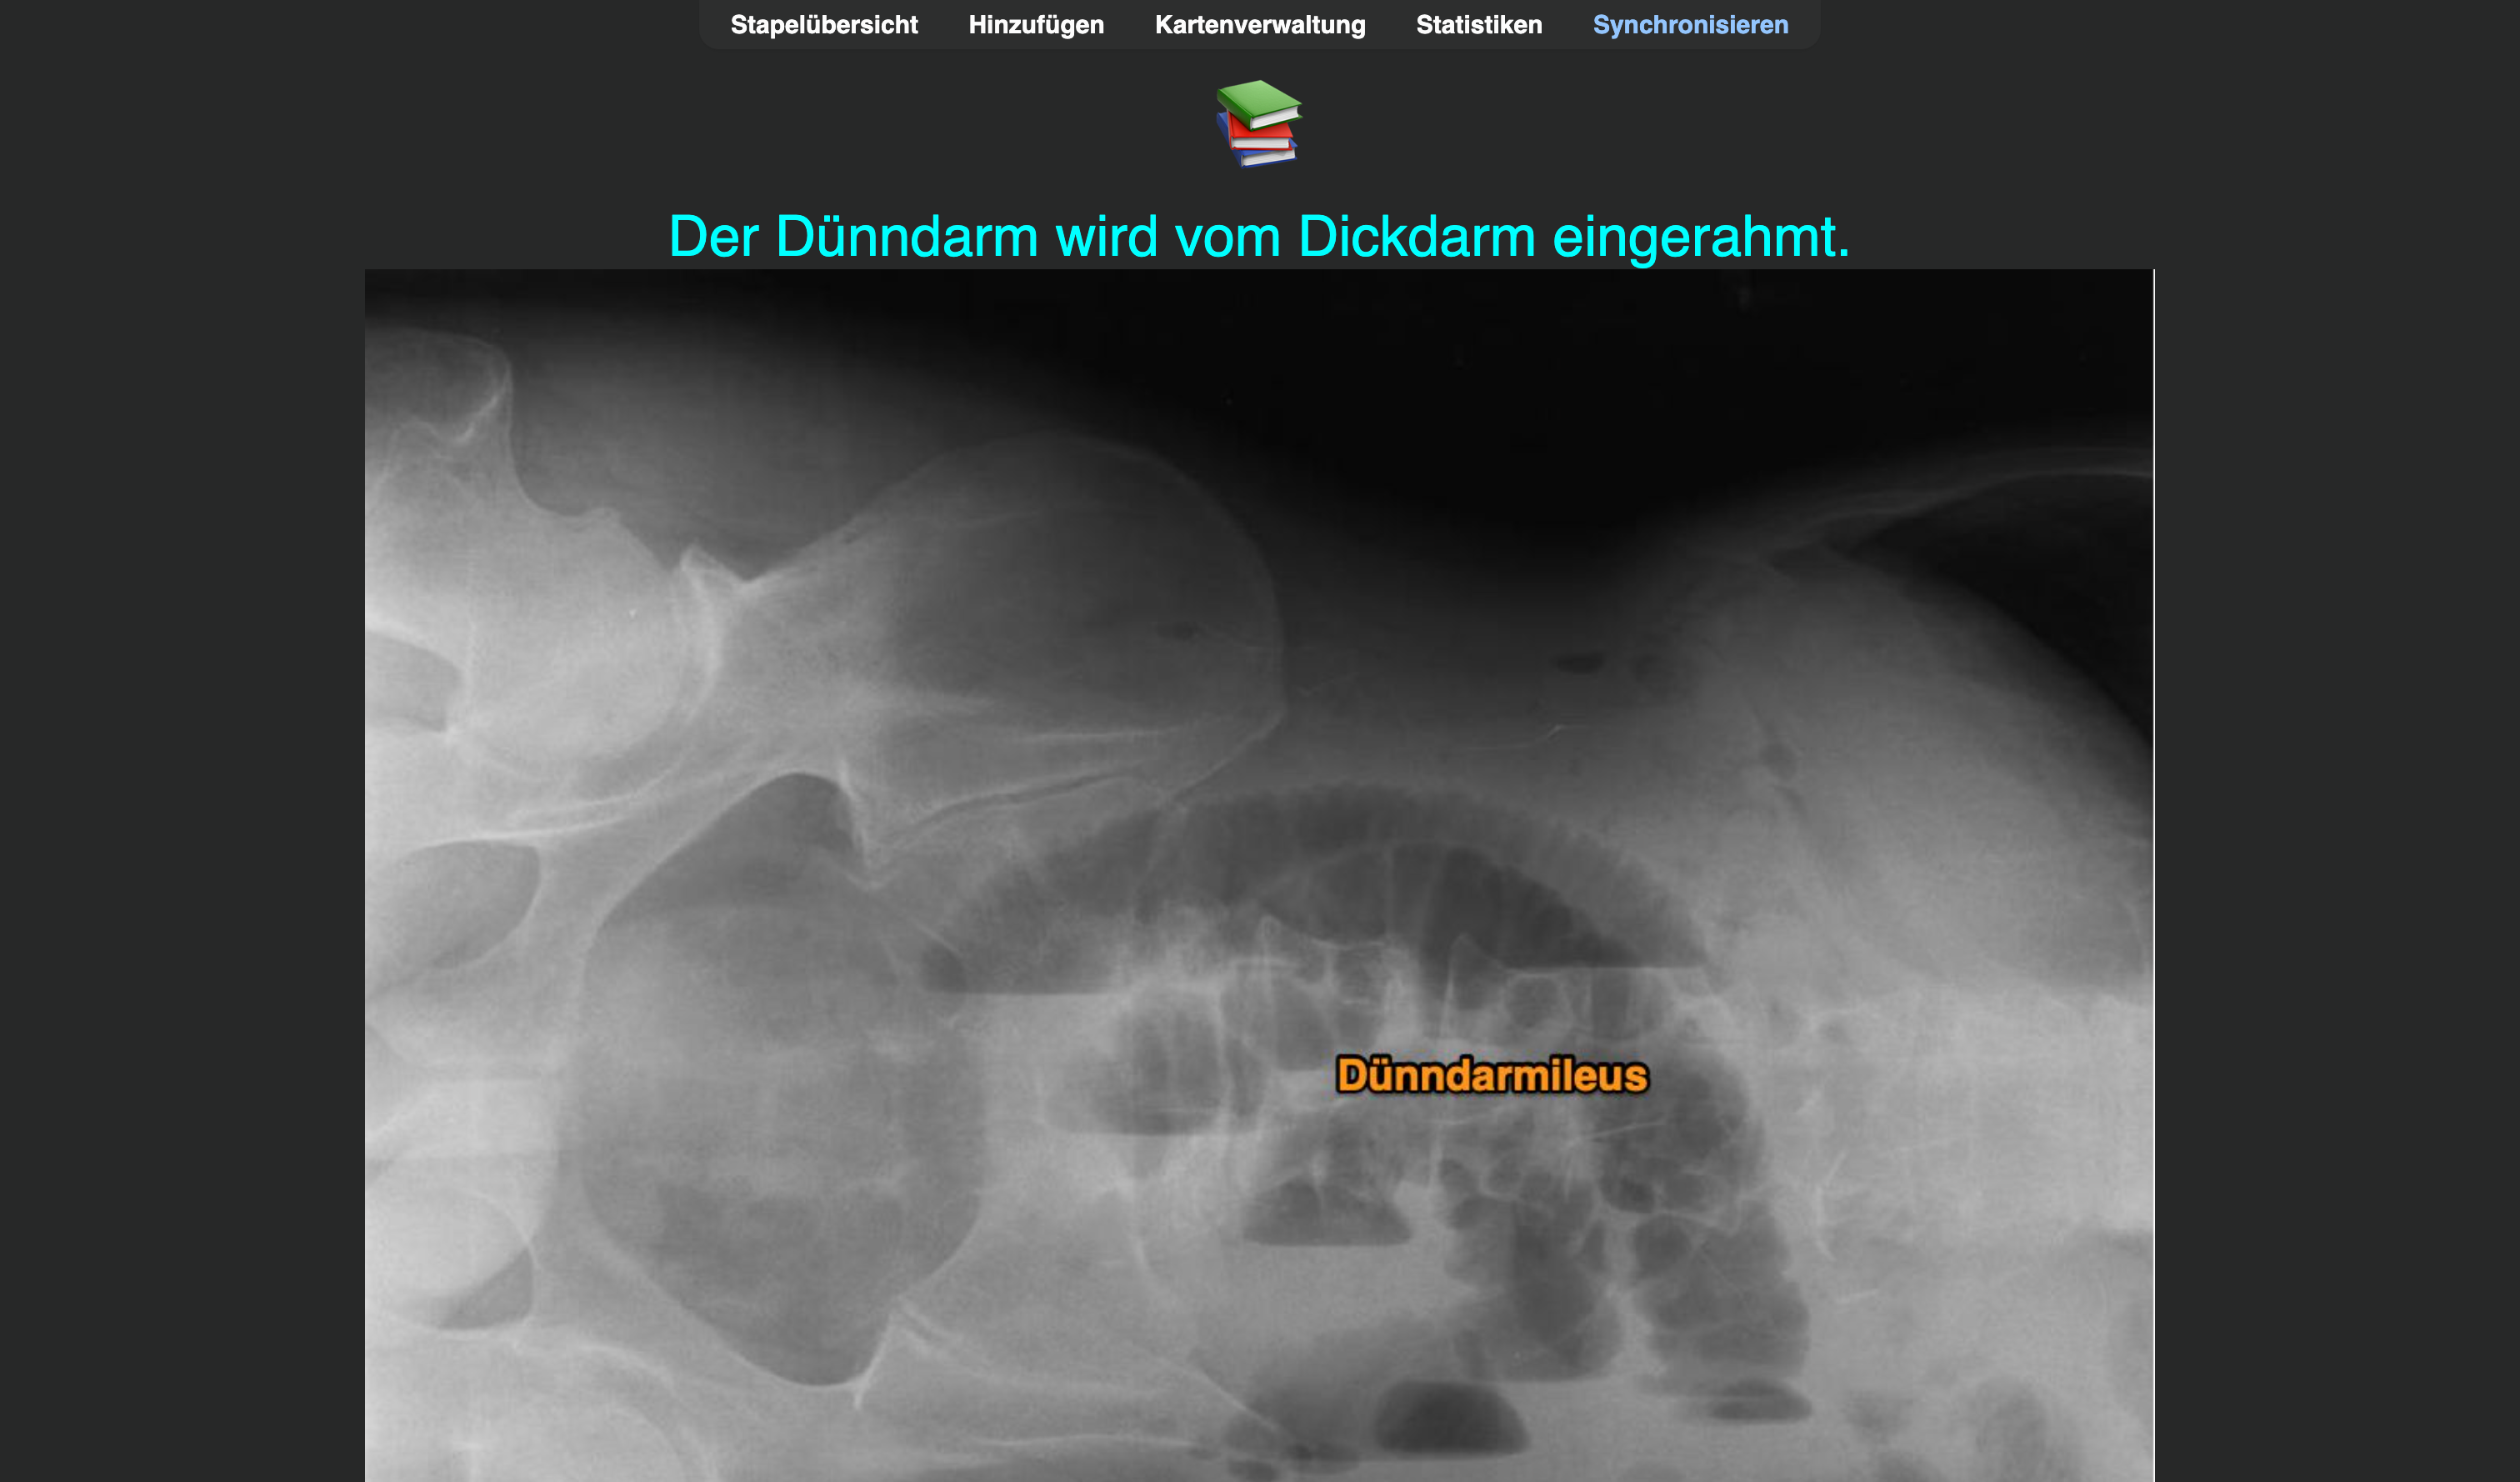

Ich konnte mir diese medizinische Information nur sehr schlecht merken:

Nach initialen erfolgreichen Wiederholungen (immer mit „Gut“ beantwortet) im weiteren Verlauf fünf Fehlversuche 😬. Also eine schlechte Karte! „Härter“ lernen bringt hier nichts; die Information ist einfach für mein Gehirn noch nicht appetitlich genug 🧀.

Also … Chunk🪓:

Background:

Bidirectional:

Auch aus der Abbildung ohne Beschriftung eine Karte erstellen.

Das dann noch analog für den Dickdarmileus durchführen. Außer einer Karte werden also bis zu sechs. Erstmal mehr Zeitaufwand, aber auf lange Sicht ein Gewinn an Wissen und Zeit 🤑.